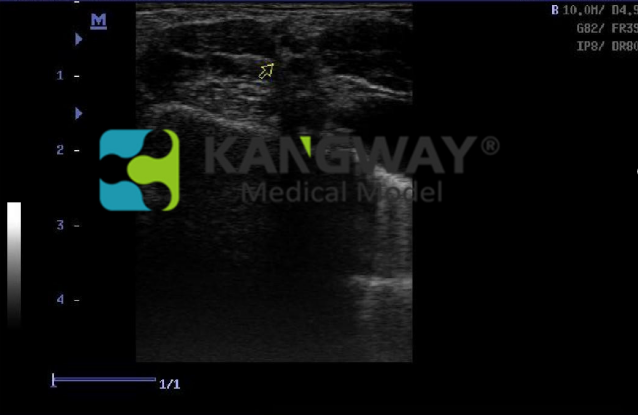

為培訓超聲引導下而專門設(shè)計的。適用于診斷超聲影像科的教學與培訓。培訓超聲引導下的周圍神經(jīng)阻滯局部麻醉操作手法以及動靜脈置管手法,可供醫(yī)生實踐并反復練習把握使用超聲引導區(qū)域麻醉和血管通路程序所必需的技能。

1. 用于提高、練習、考核超聲引導穿刺術(shù);

3.由仿生人體硅膠制成,真實的人體組織觸感,且該材料與人體組織擁有相同的聲學特性,超聲圖像極為真實,且堅固耐用,可大大減少損耗,節(jié)約成本;

4. 包含根直徑為2mm的神經(jīng)支和二根直徑為1mm的神經(jīng)支

9.可與市面上任何超聲設(shè)備結(jié)合完成超聲影像訓練與考核。